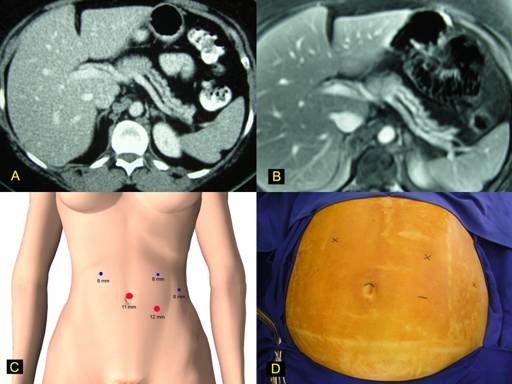

A 37-year-old female with previous history of radical mastectomy for bilateral breast cancer due to BRCA2 mutation presented an acute pancreatitis episode. Radiologic investigation disclosed an intraductal pancreatic neoplasm located in the neck of the pancreas with atrophy of body and tail (Figures 1a-b). Main pancreatic duct was enlarged. Surgical decision was to perform a laparoscopic subtotal pancreatectomy using the Da Vinci robotic system. The patient is initially placed in supine position and a cushion is placed below its left flank, thus tilting the patient toward the right lateral decubitus position by approximately 30°. An orogastric tube is inserted and removed at the completion of the procedure. Using an open technique, a 11-mm trocar is placed in the supraumbilical position; through this port, robotic camera is introduced, and 4 additional ports are placed: three 8-mm and one 12-mm as displayed in Figures 1c-d.

FIGURE 1. Robotic pancreatic resection.